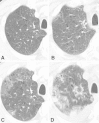

Fig. 2

The progressive multiple lung shadows were detected with chest CT. Twelve days before admission (a), on the 2nd hospital day (b), 11th day (c) and 19th day (d)